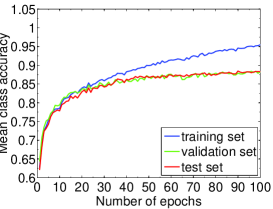

We highlight that training-relevant hyper-parameters can significantly affect the convergence of cost function, the learning speed and the generalization capability of the network. Their impacts are demonstrated via the learning curves of MCA on training, validation and test sets shown from Fig. 4 to Fig. 8. In each figure, we focus on one hyper-parameter while the others are set to their optimal values in Table 2.

Fig. 4 LABEL:sub@subfig:lr1 indicates that when learning rate is small, e.g., , the learning process is so slow that the MCA of the three sets have not become stable in epochs. Properly increasing the learning rate effectively improves learning efficiency and the MCA becomes stable in epochs, as shown in Fig. 4 LABEL:sub@subfig:lr2. At the same time, an over-large learning rate, e.g., , will destabilize the learning process and degrade the classification performance. Also, Fig. 5, 6 and 7 demonstrate the impacts of mini-batch size, momentum and weight decay, respectively.